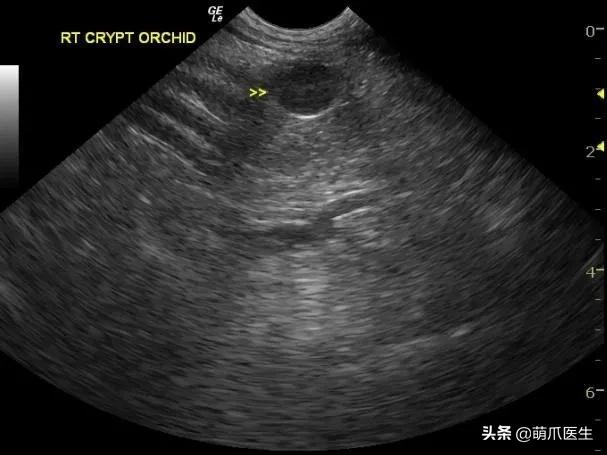

有些 消失的蛋蛋 ,是直接可以用手摸到的,有些就 只能通过B超找到 。